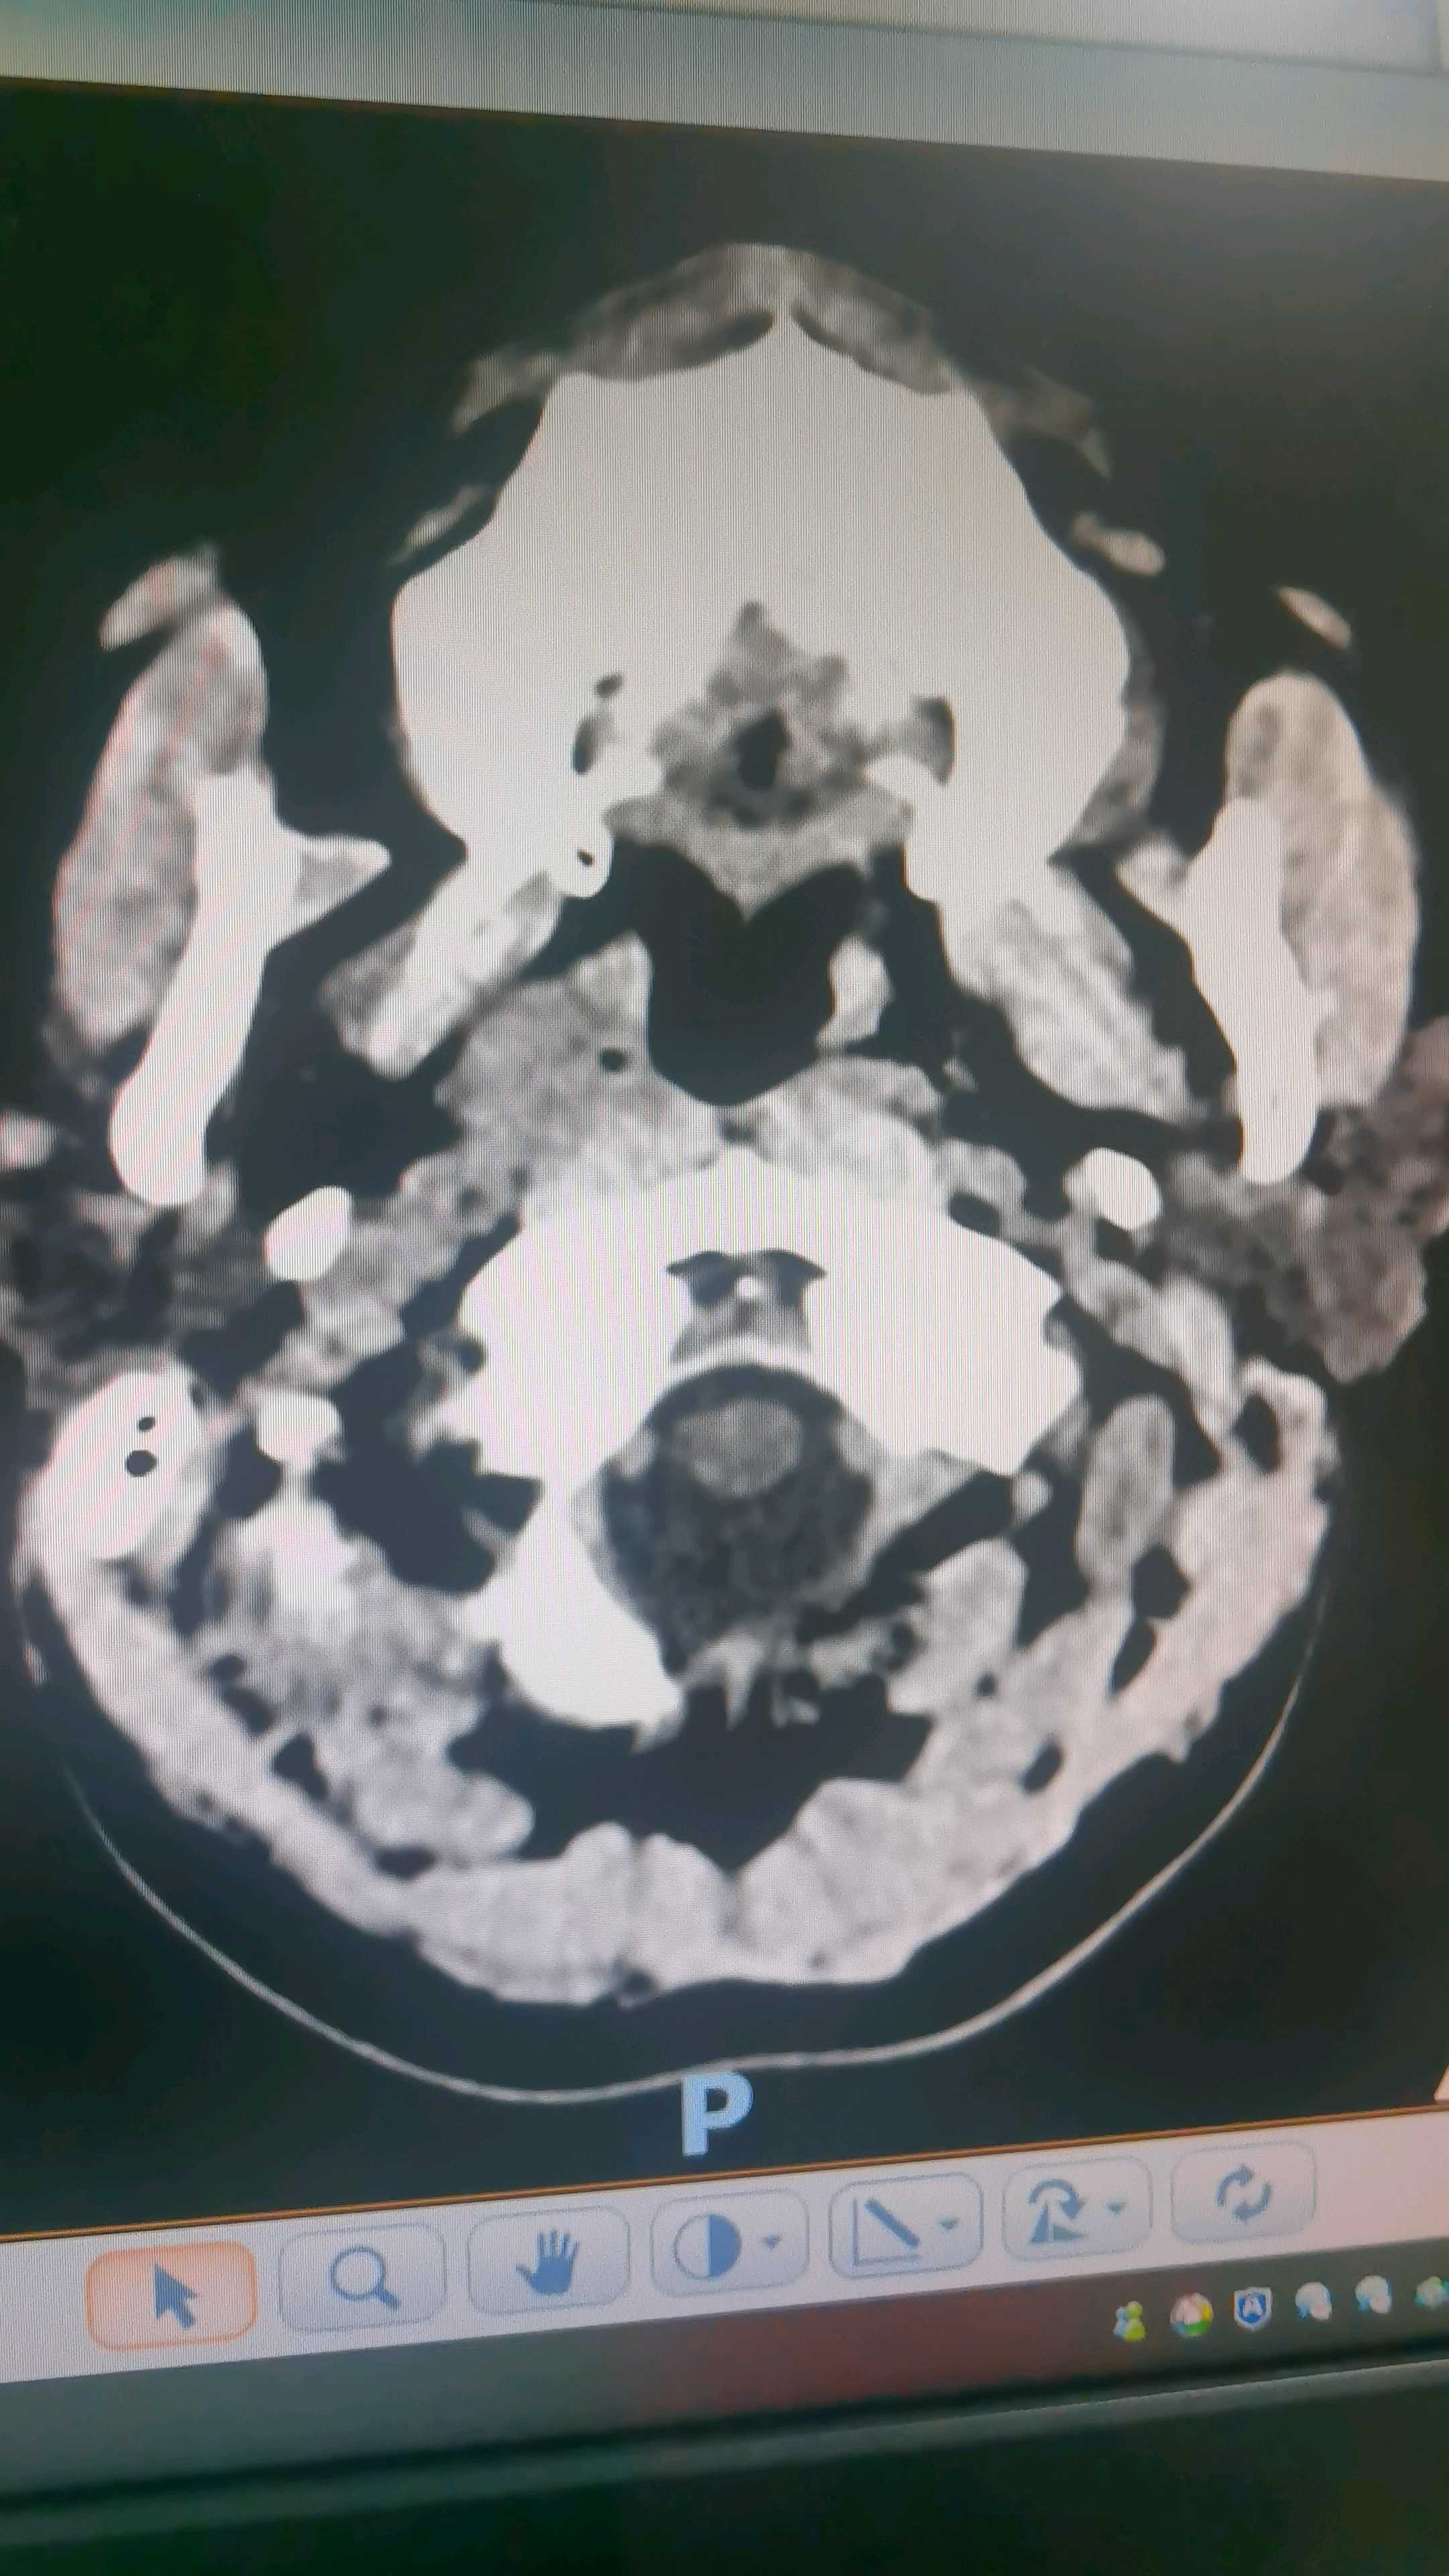

我院cta